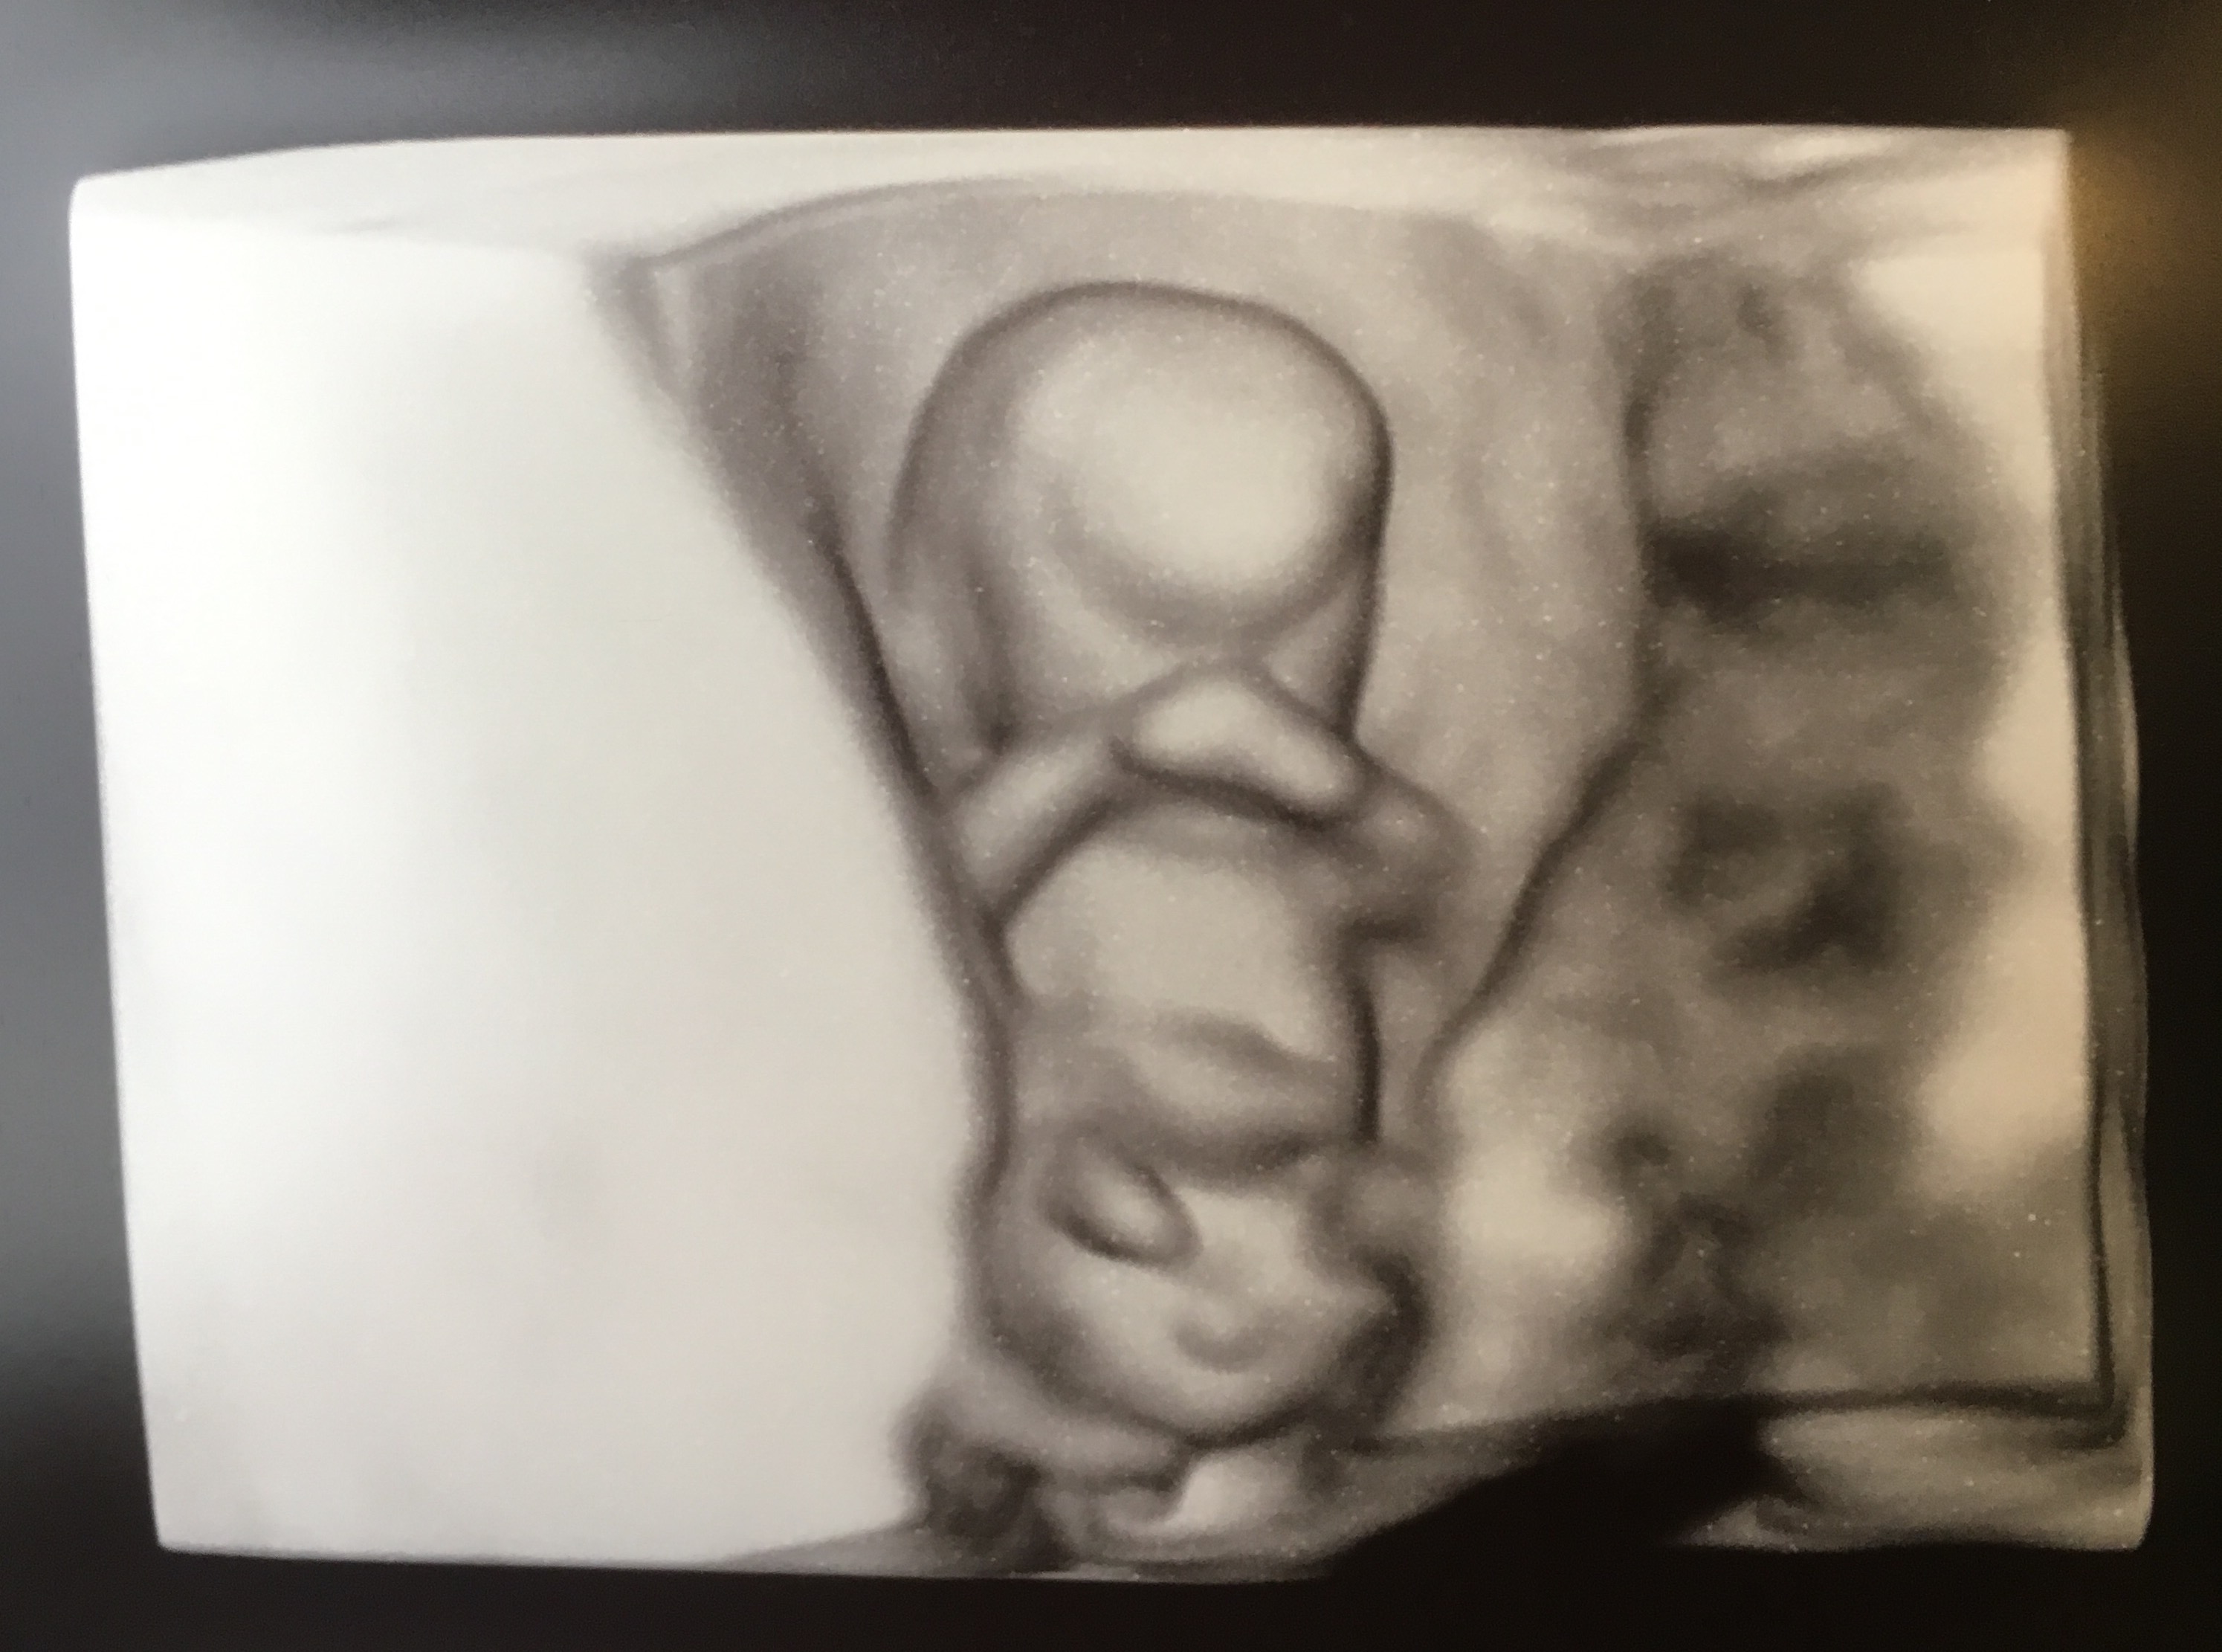

3d 11 Week Ultrasound

Hyperechoic Yolk Sac Left 2d Image Right 3d Image 11 Weeks And